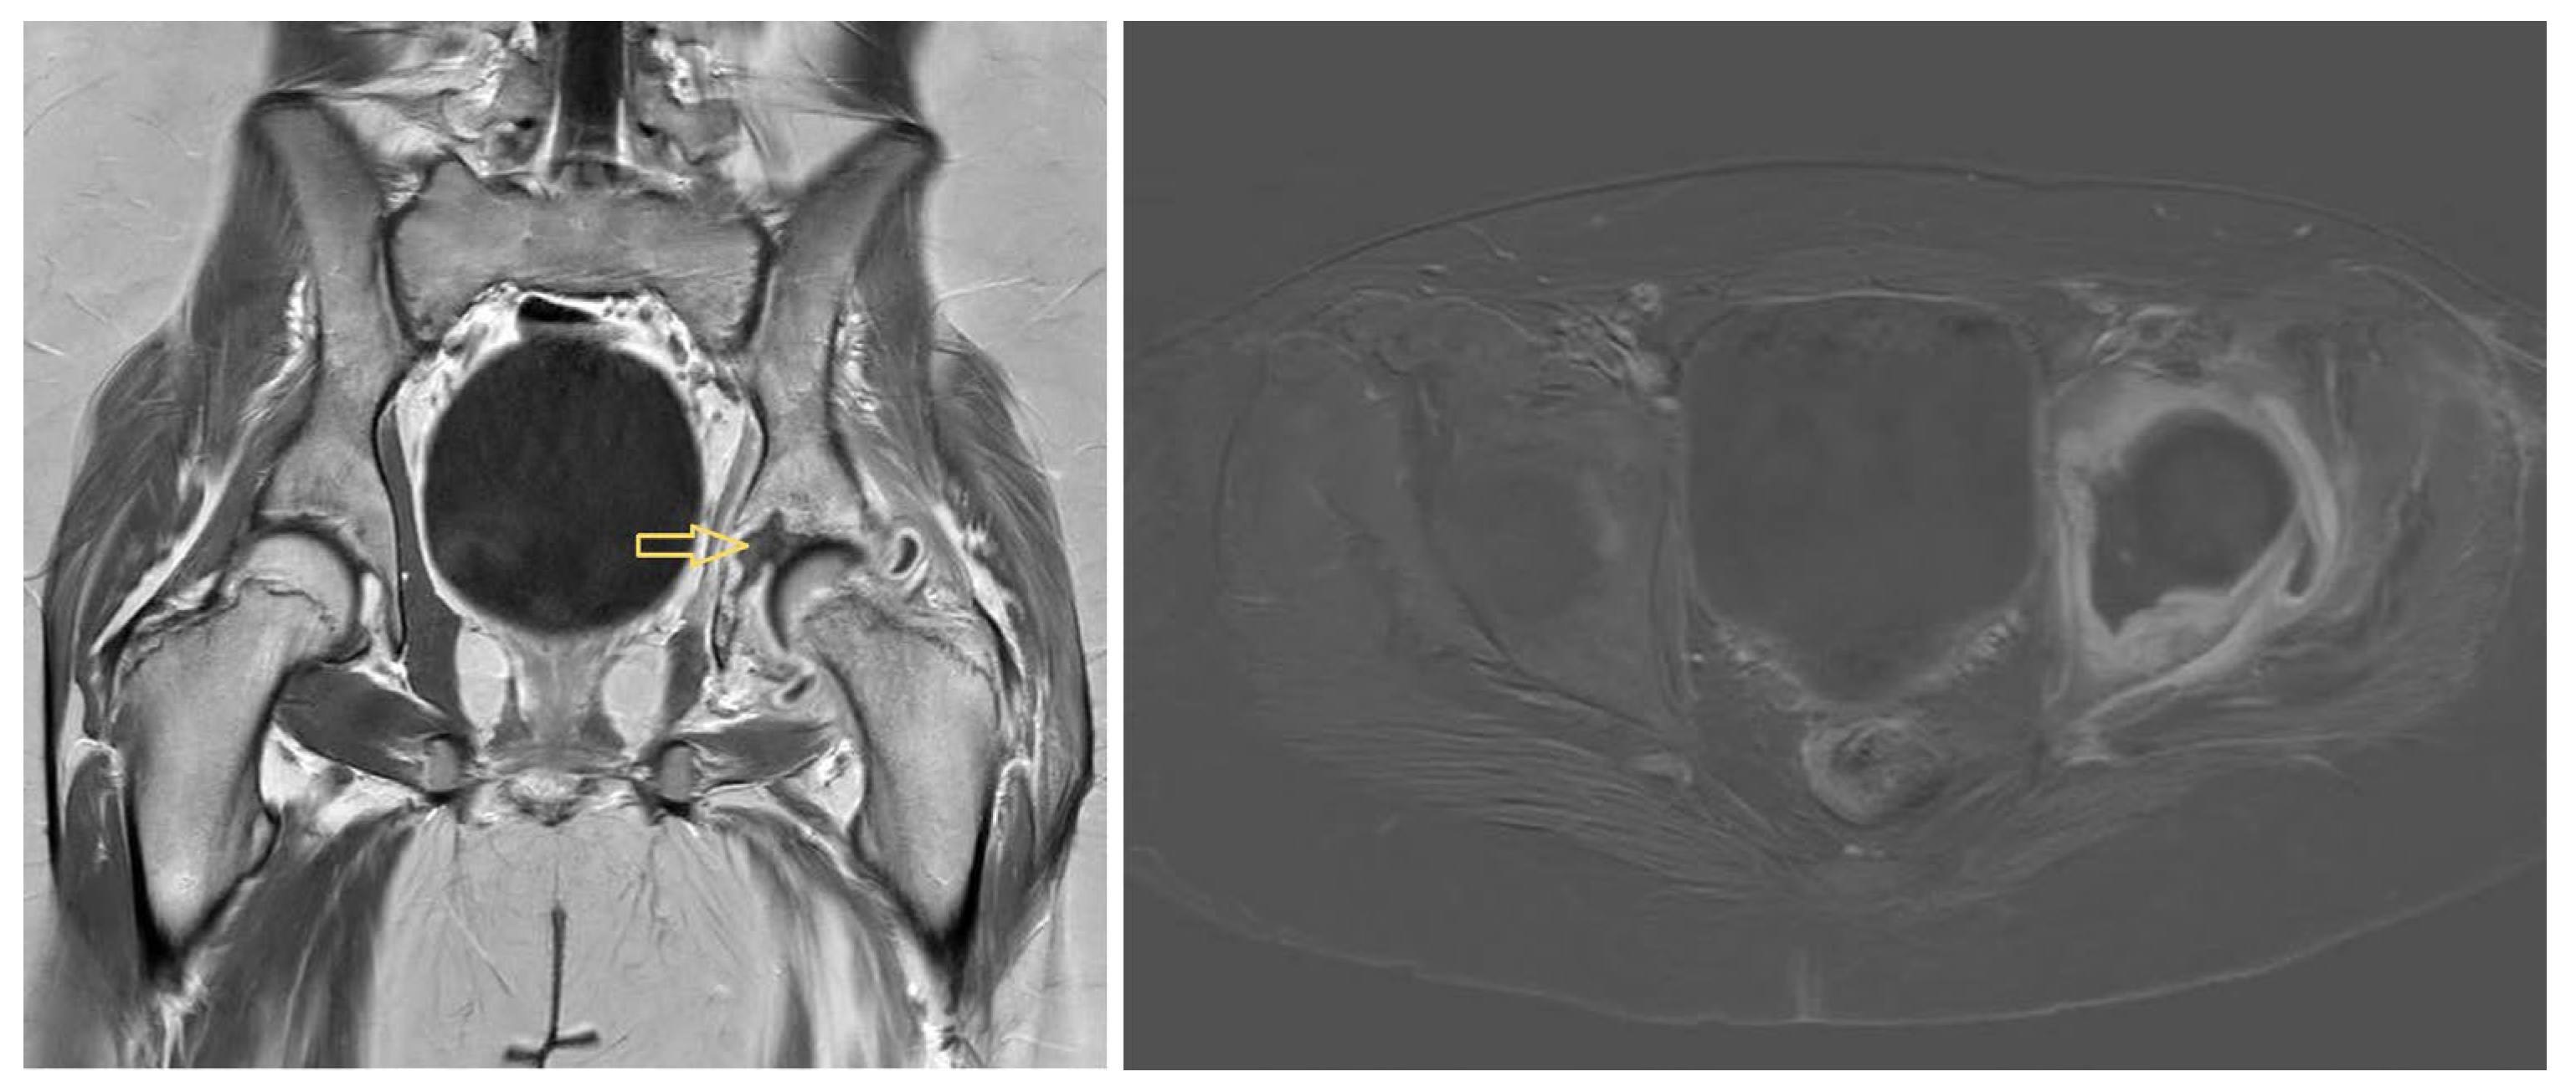

3.1.1. Patient 1

3.1.2. Patient 2

3.1.3. Patient 3

4.3. Diagnostic Imaging